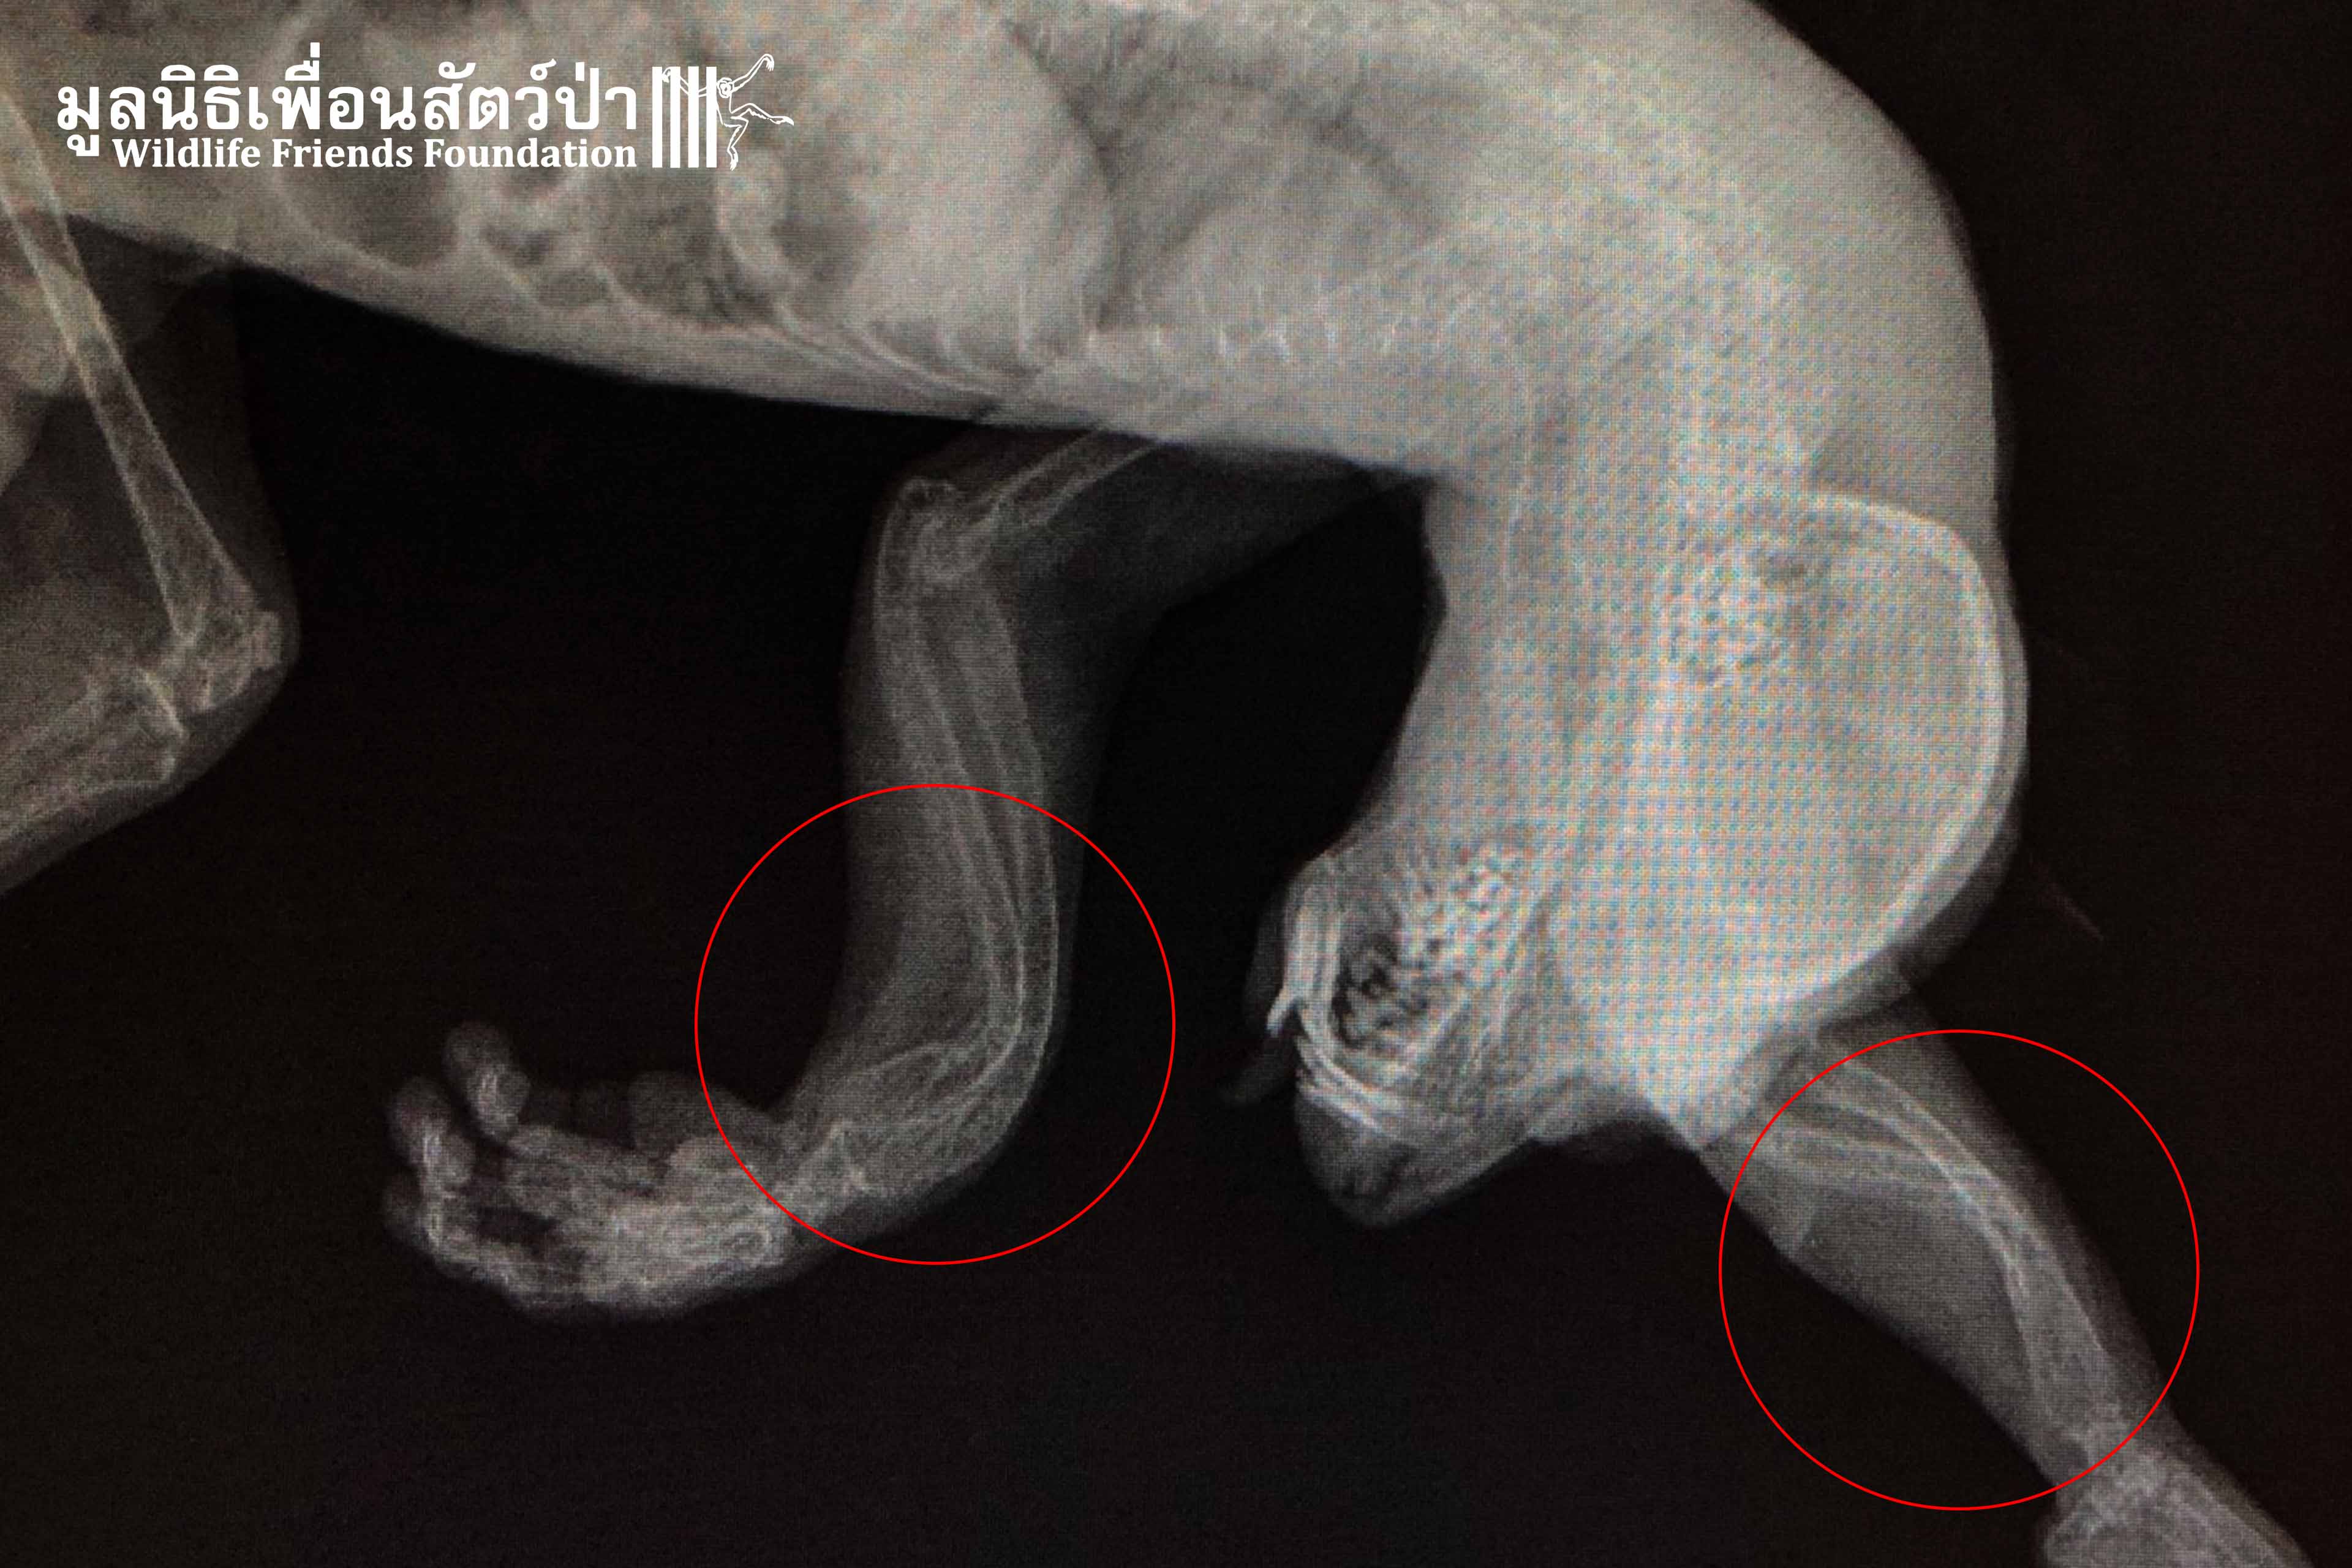

The Veterinary Team did an initial examination and x-ray, they found Tufa has a severe case of metabolic bone disease (MBD) which is commonly found in most vertebrates. MBD is caused by improper nutrition, calcium deficiency, and vitamin D deficiency. In this case, Tufa’s limbs are deformed and in a fragile state which makes it very difficult for him to crawl or climb in a tree the way a slow loris is supposed to.

Currently, Tufa is under close care by the Vet Team. He is receiving a new diet plan and daily physiotherapy sessions with Chin, the slow loris that also has metabolic bone disease (Read